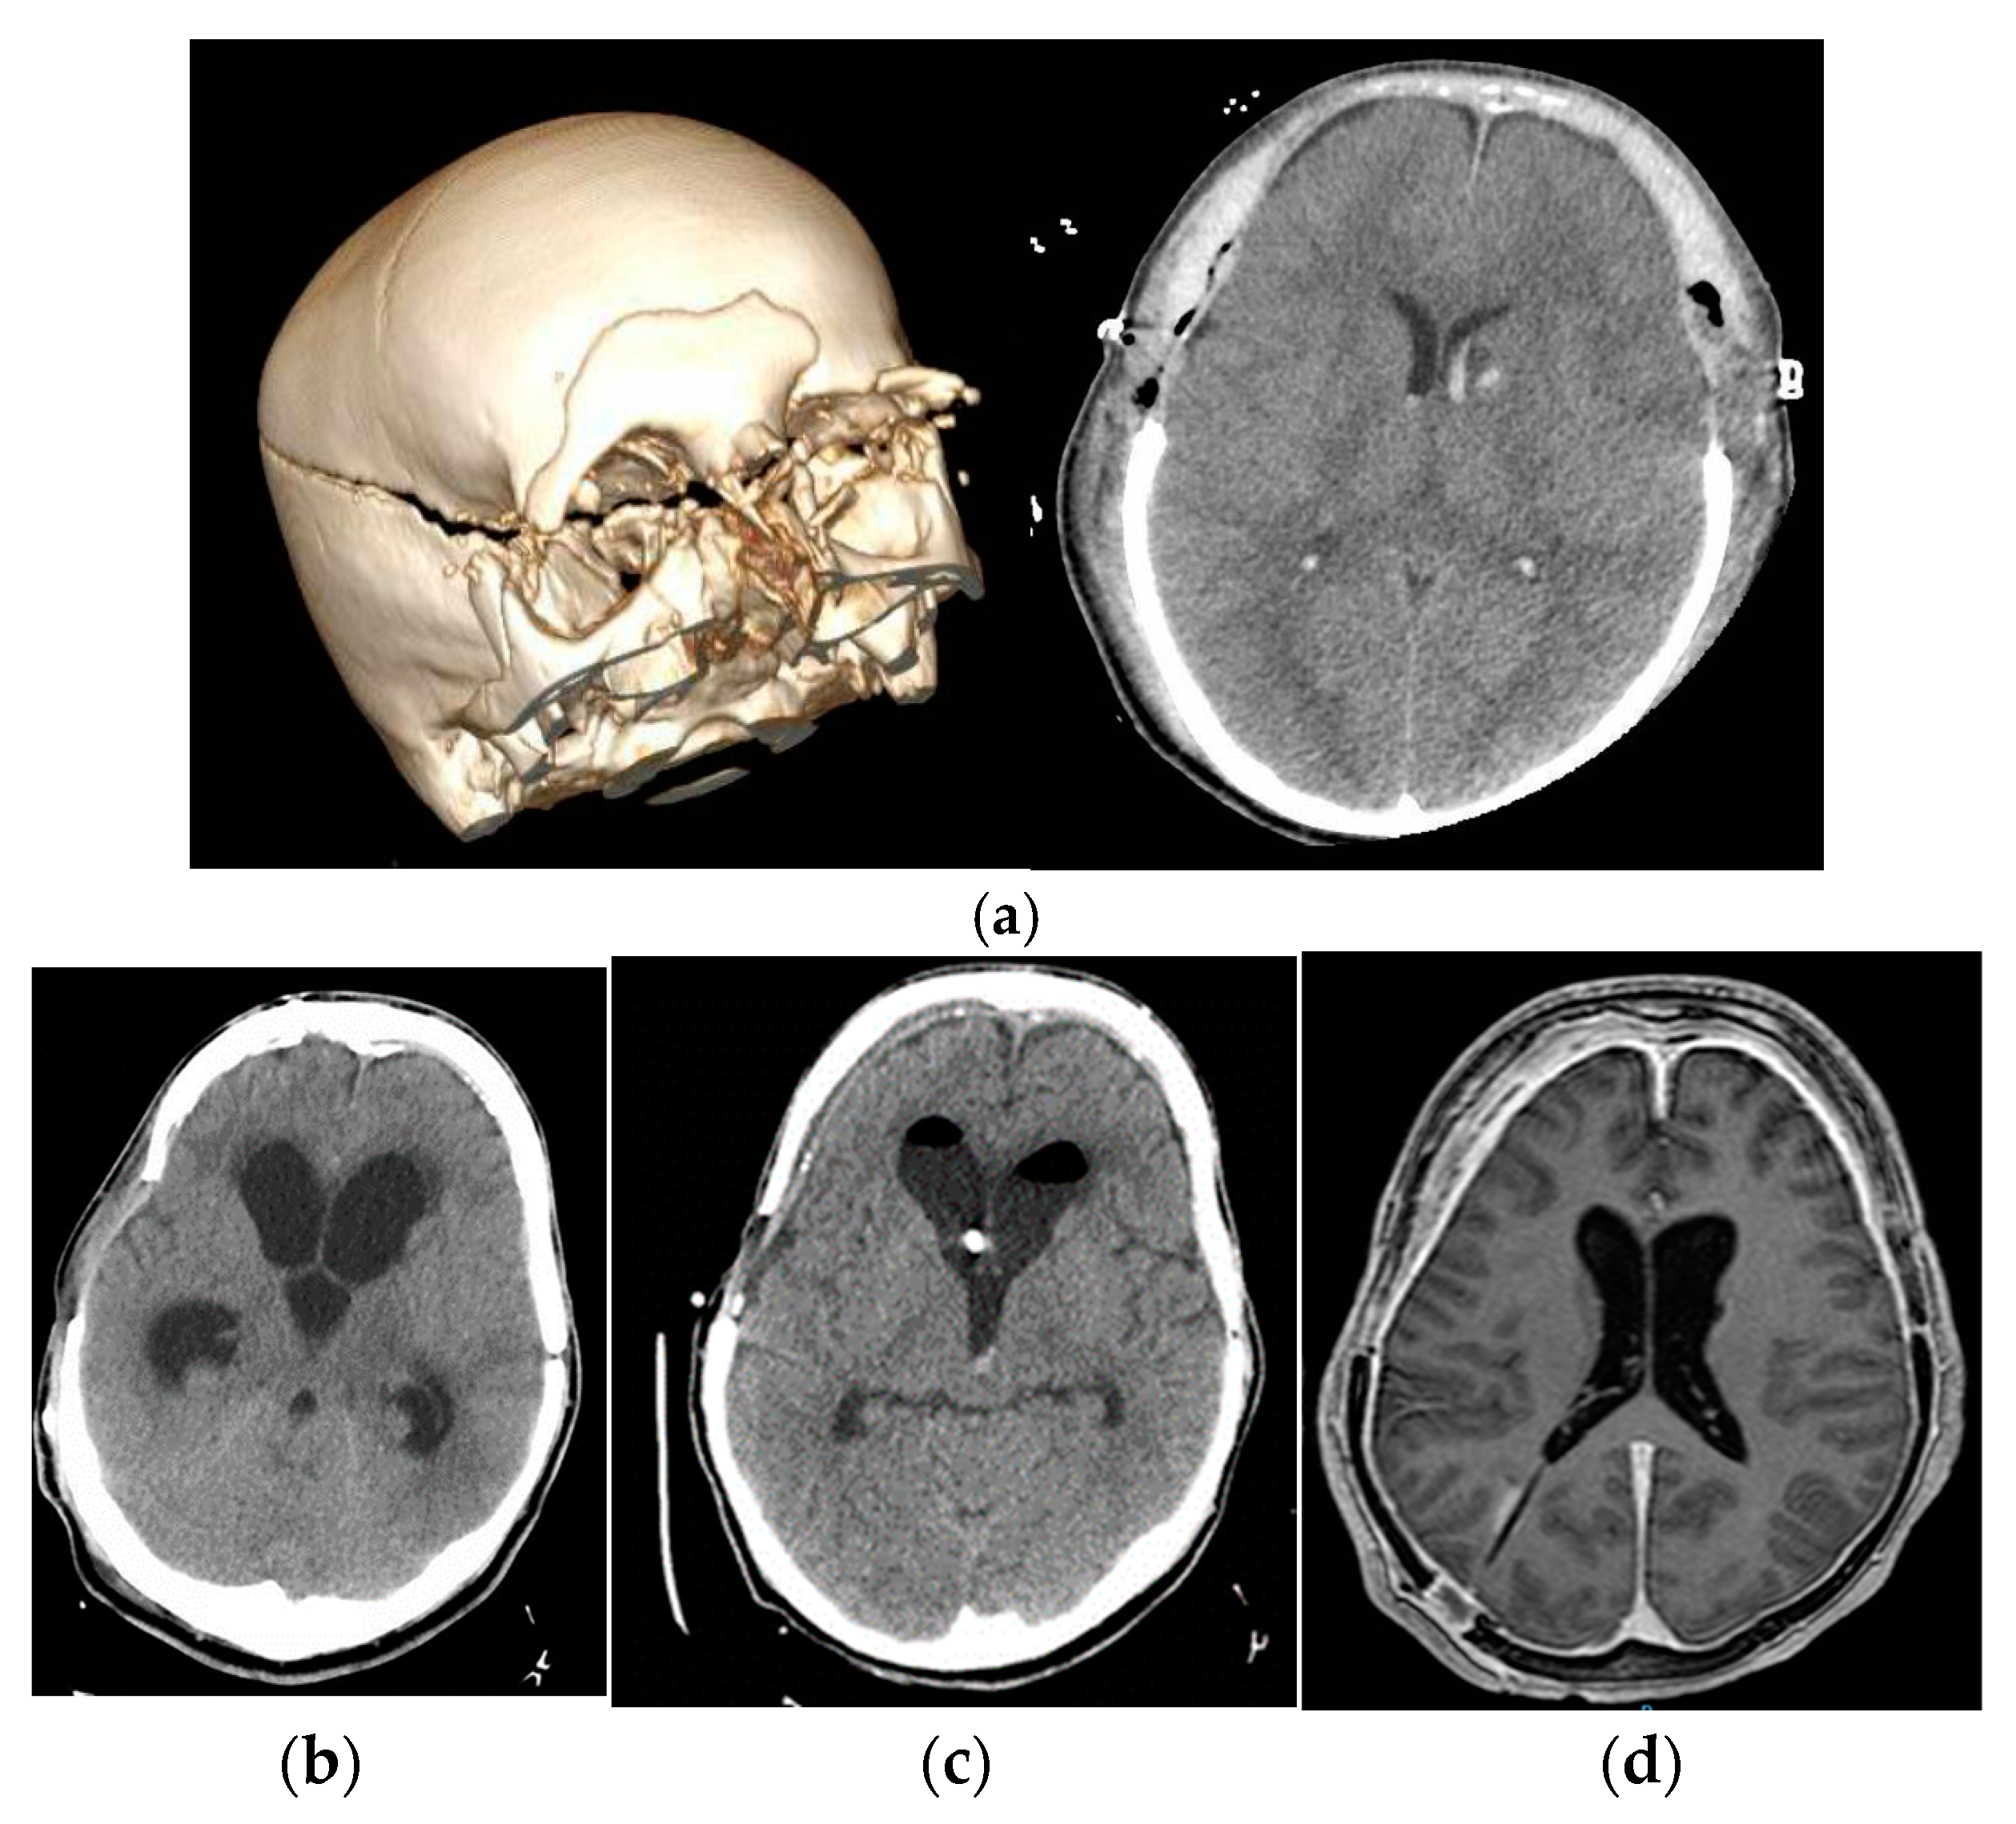

The authors added Figure 5 in Section 3.5:

Figure 5. Image (a) pre-surgical and immediate post-surgical images of patient n 5 (b): development of hydrocephalus being treated with EVD. Image (c): normalization of ventricular size at day 25 after subzero drainage. Image (d): new ventricular dilatation despite definitive shunt treated by a new wide external catheter in left ventricle. Image (e): magnetic resonance imaging at discharge. Hyperdrainage signs are seen with ventricular size almost normalized.